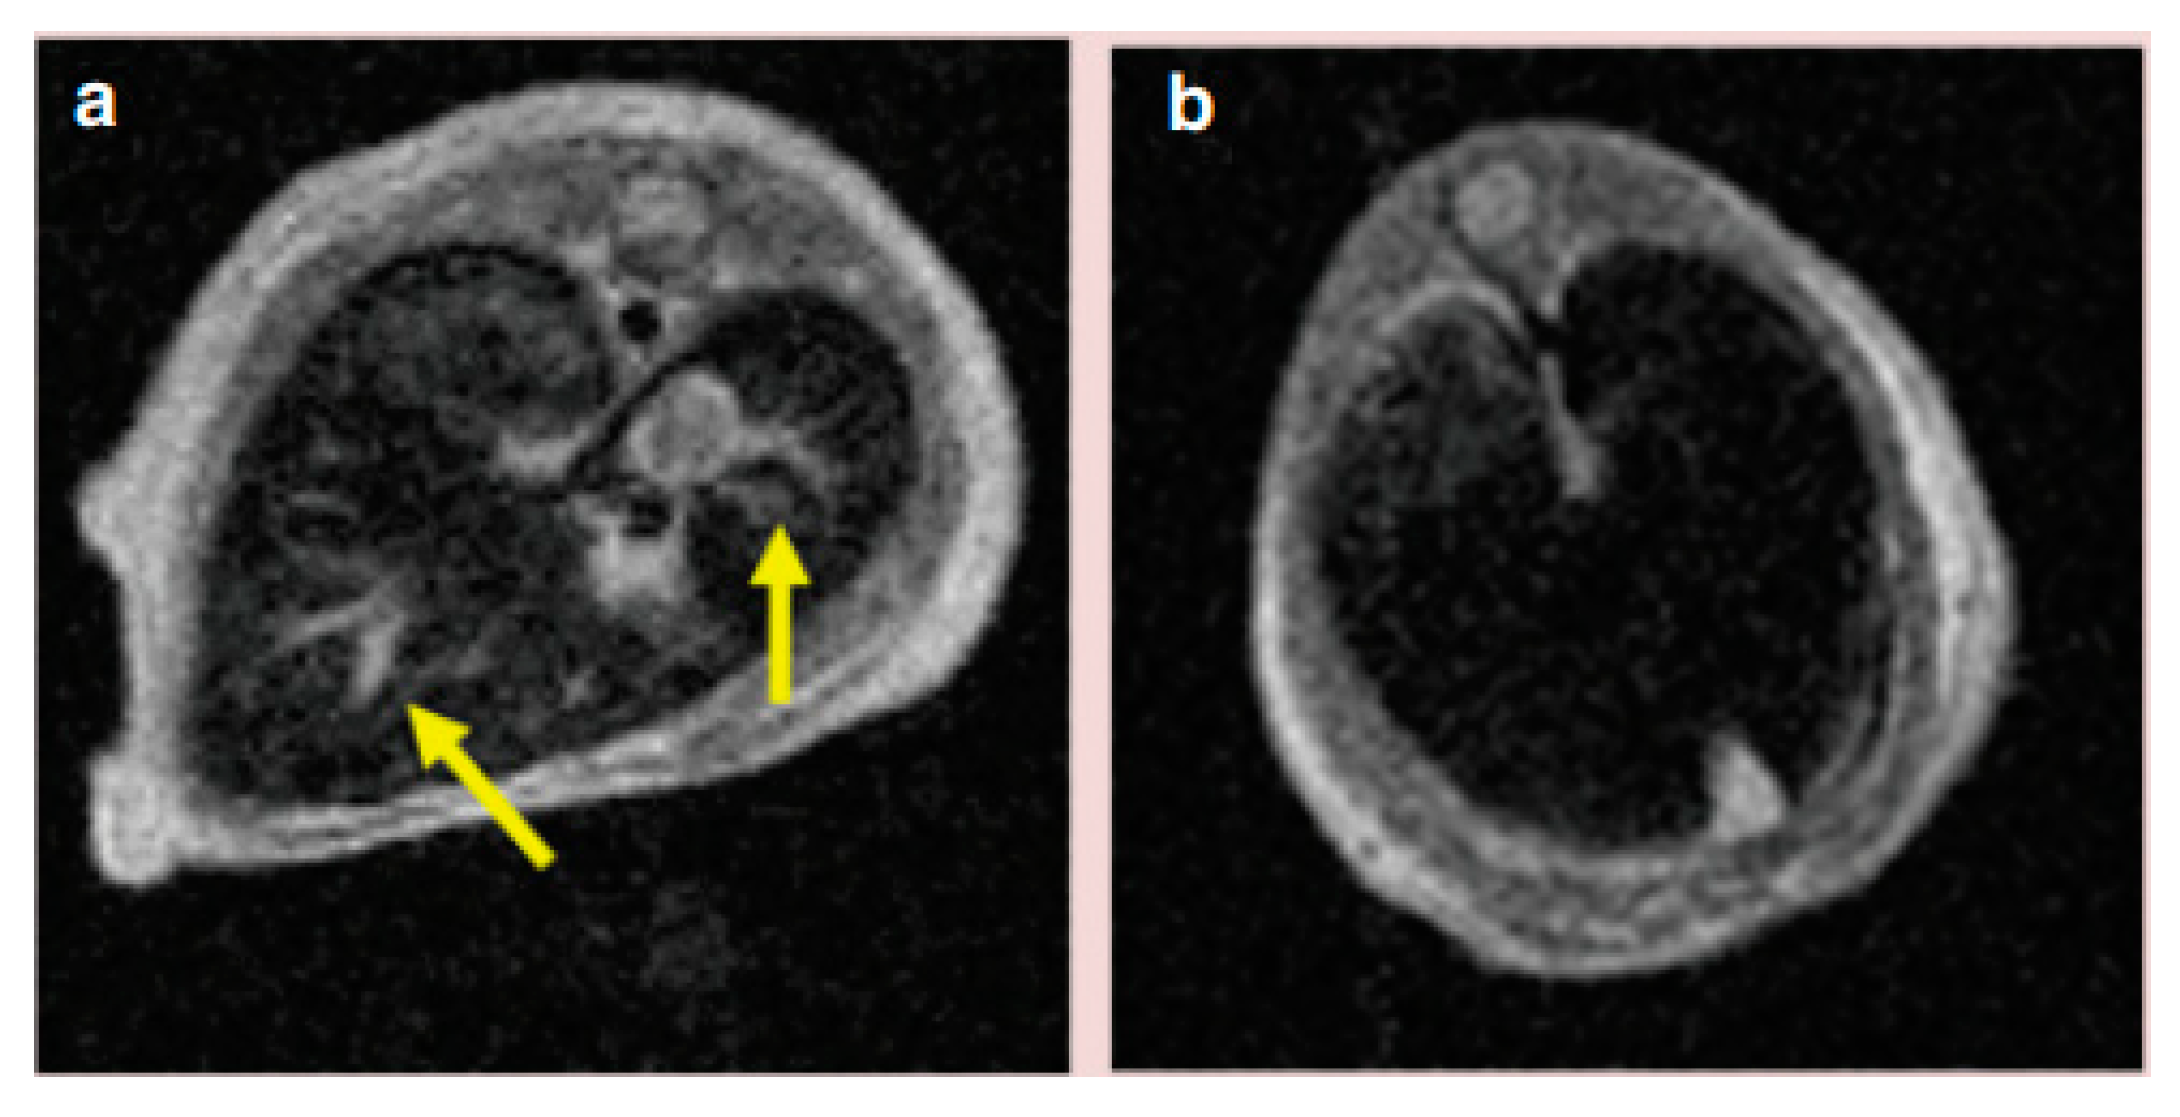

- Xie, H.; Zhu, Y.; Jiang, W.; Zhou, Q.; Yang, H.; Gu, N.; Zhang, Y.; Xu, H.; Xu, H.; Yang, X. Lactoferrin-conjugated superparamagnetic iron oxide nanoparticles as a specific MRI contrast agent for detection of brain glioma in vivo. Biomaterials 2011, 32, 495–502. [Google Scholar] [CrossRef]